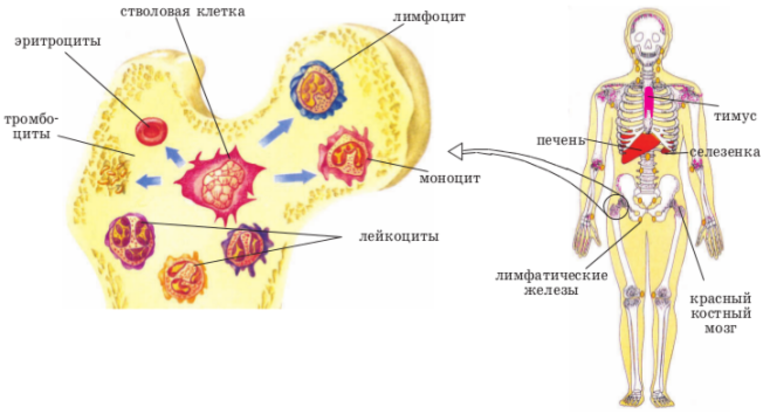

Изучение костного мозга: анатомия и функции

Раздел: Фотогалерея мыслей